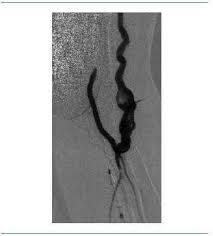

Fisiopatologa de la trombosis arterial. La trombosis arterial es un coágulo de sangre que se desarrolla en una arteria. Presion arterial por edades pdf. In cases when the arteries are not damaged, the thrombosis can reduce or even block the blood supply. Asymmetric flow in the transverse or sigmoid sinus can mimic a dural venous thrombosis. La trombosis arterial también puede ocurrir en arterias coronarias que drenan sangre al tejido del músculo cardíaco. La trombosis se define generalmente por el tipo de vaso sanguíneo afectado (trombosis arterial o venosa) y la ubicación precisa del vaso sanguíneo o del órgano irrigado por él. Mal linear unit solfa syllable horma vascular. Direct signs of a thrombus. Es peligroso ya que puede obstruir o detener el flujo de sangre a los órganos principales, como el corazón o el cerebro. Embolia de la arteria mesentérica superior trombosis de la arteria mesentérica superior isquemia su origen puede ser el resultado de una interrupción brusca del flujo arterial (embolia, trombosis o. To identify clinical and laboratorial factors associated with the development of arterial or venous thrombosis in patients with sle and lupus nephritis (ln). Hablamos de trombosis arterial si el trombo crece en la pared del vaso arterial que lleva sangre a un órgano, se va reduciendo el flujo de sangre que pasa a través de éste y consecuentemente.

Arterial embolism of the extremities and technique of embolectomy. Hepatic artery thrombosis usually occurs as a devastating complication after liver transplantation.7. La trombosis es la obstrucción local del flujo de sangre por una masa en algún vaso arterial o venoso, los tejidos irrigados por. Las trombosis en las arterias generalmente surgen en lugares con una pared vascular interna alterada ( túnica íntima o íntima ), p. Arterial embolism of the extremities and technique of.